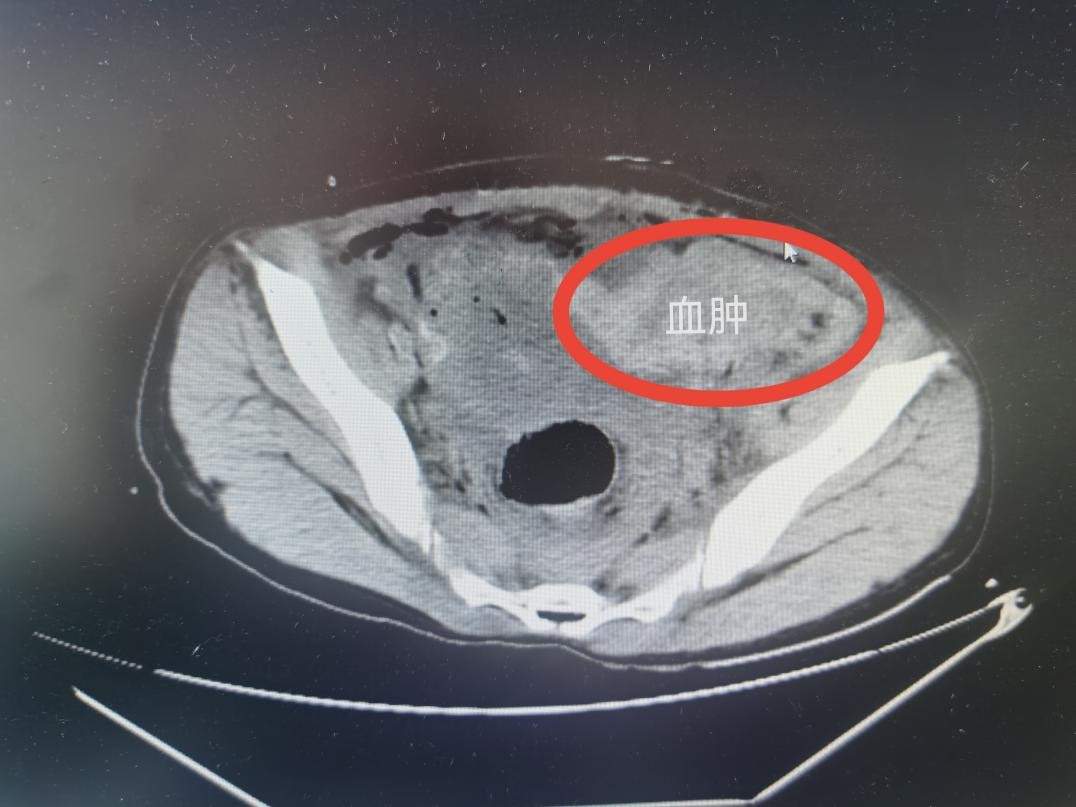

卵巢血肿

保命也要保子宫一场跨越3000多公里的紧急云救援